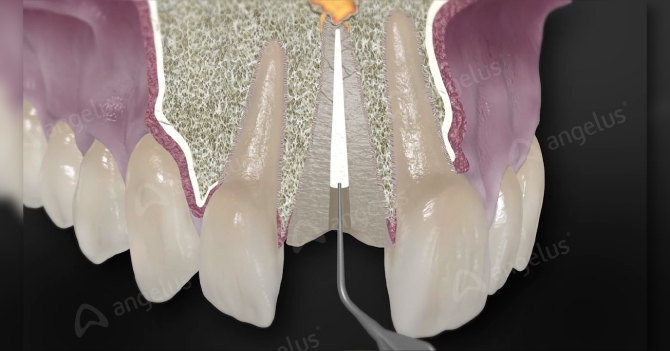

Pasta biocerámica para apósito intraconducto.

-Apósito intraconducto en el tratamiento endodóntico de dientes con necrosis pulpar y retratamientos;

-Apósito intraconducto en casos de perforaciones, reabsorciones externas e internas, previo al uso de BIO-C® REPAIR, MTA REPAIR HP y MTA ANGELUS;

-Rizogénesis incompleta;

-Traumatismo dental.